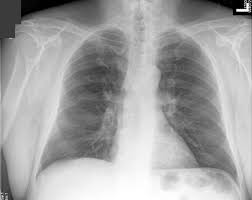

What is a chest X-ray?

A chest X-ray is exposing the chest briefly to radiation to produce an image of the chest and the organs in the chest. An X-ray film is positioned against the body opposite the camera,and there is two view anterior-posterior and lateral view. which sends out a small dose of a radiation beam. As the radiation penetrates the chest wall, it is absorbed in varying amounts by different body tissues depending on the tissue's composition of air, water, blood, bone, or muscle. Bones, for example, absorb much of the X-ray radiation while lung tissue (which is filled with mostly air) absorbs very little, allowing most of the X-ray beam to pass through the lung.Watch this video:

Systematic Review:

- See XRay Interpretation

- Compare findings from side to side

- Note if patient is lordotic or kyphotic

- Note patient rotation

- Spinous processes midway between clavicle heads

- Lines and Tubes

- Bones

- Soft tissues

- Pleural spaces

- Mediastinum

- Cardiovascular structures

- Lung parenchyma

- Infradiaphragmatic areas

- Hilum is higher on the left

- Hemidiaphragm is lower on the left

- May be variable in older patients

- Right hemidiaphragm sharply outlined

- Left hemidiaphragm sharply outlined lateral to apex

- Localize any lesion on both lateral and AP

- Endotracheal Tube should be above carina

- Usually overlies 5-6th vertebrae

- Trace intravenous lines along entire course

- Trace Nasogastric Tubes along entire course